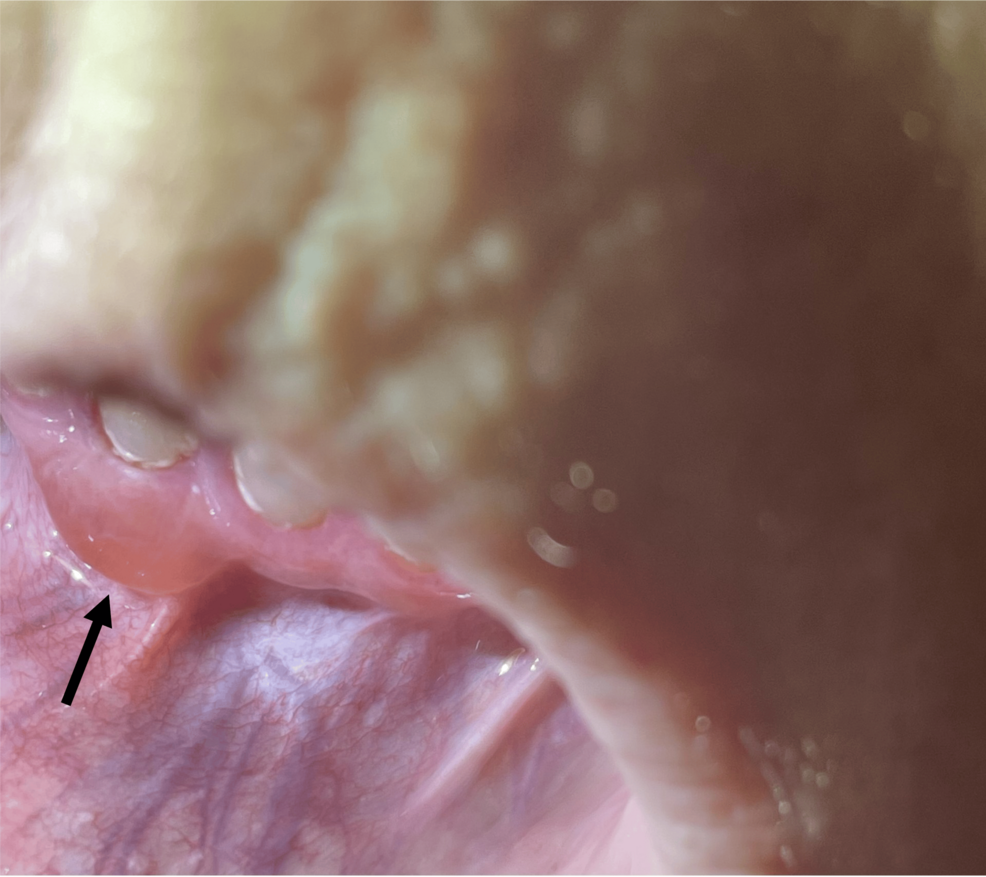

The PatientS condition Involved Blisters In The Mouth (Gingival Involvement) Alongside Those On The Skin. this Concurrent Presentation Is Not Typical And Delayed Initial Diagnosis. Accurate And Timely Diagnosis Is Crucial For Effective treatment And To Prevent Potential Complications.

Yes, oral Involvement, Affecting The Gingiva And mucous membranes, Can Occur in certain specific cases.